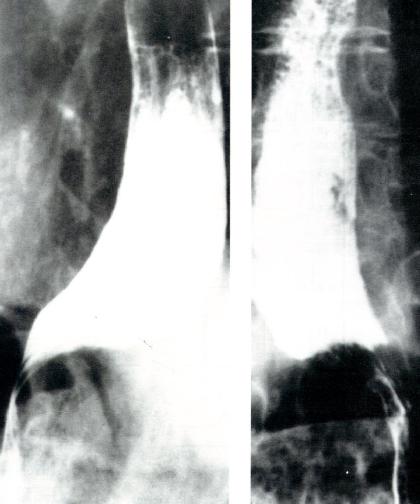

食管X线检查

X线吞钡可用于观察食管并显示食管是否扩张。贲门失弛缓症的特征性X线表现为胸部食管扩张伴液平。LES逐渐变细使食管呈现鸟嘴样外观(图2.7)。

贲门失弛缓症的食管X线表现

图2.7贲门失弛缓症的食管X线表现。

食管体可呈扩张、张力低或直径正常但蠕动减少等不同的表现(图2.12)。

硬皮病患者的吞钡表现

图2.12硬皮病患者的吞钡表现。硬皮病X线所见可与贲

门失弛缓症相似,仅LES开口增大而不同。